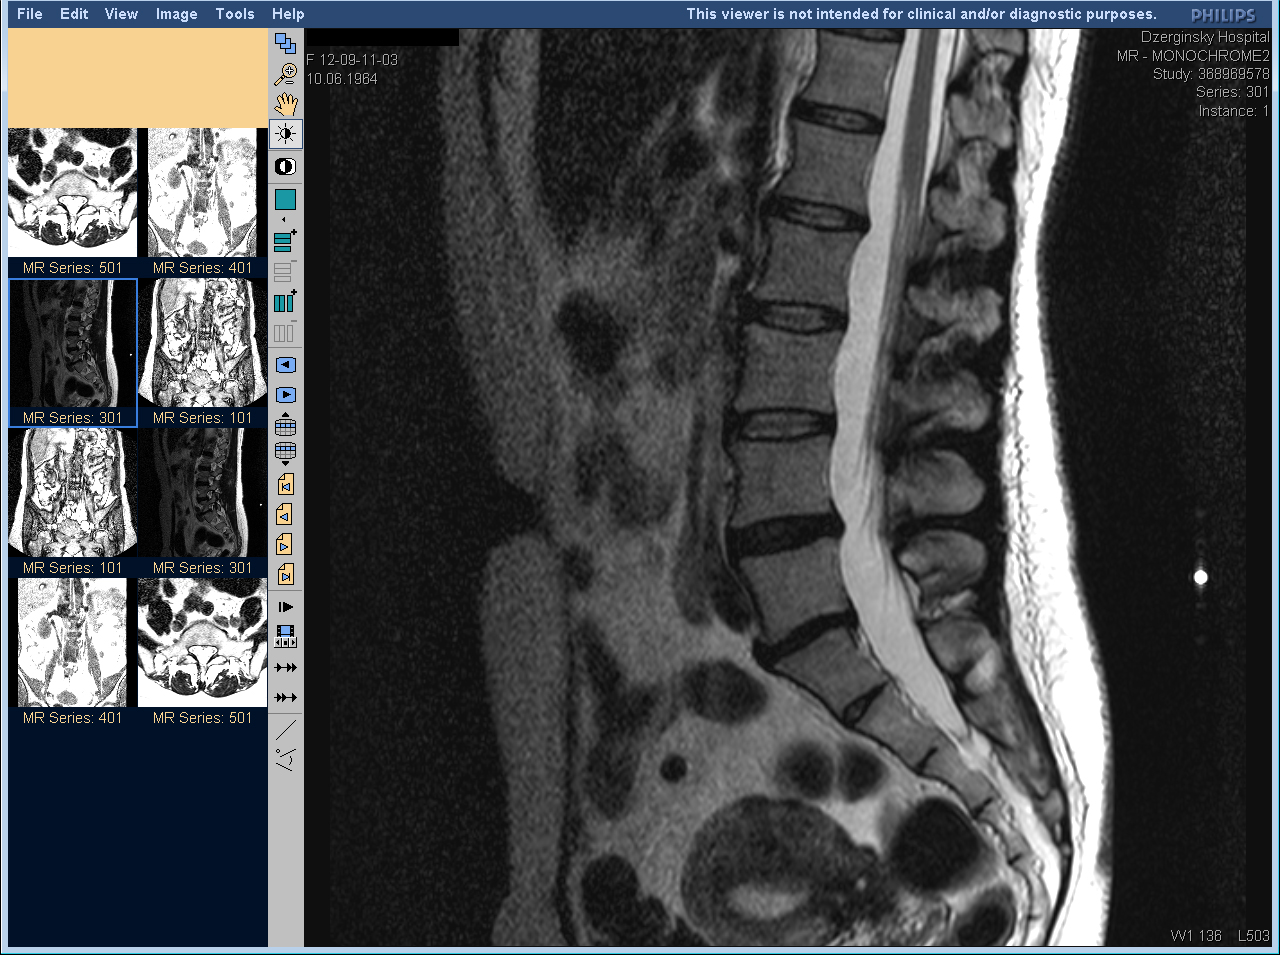

МРТ позвоночника - как выглядит грыжа спины. Магнитно-резонансная томография

КАК ЧИТАТЬ МРТ ПОЯСНИЧНОГО ОТДЕЛА ПОЗВОНОЧНИКА САМОСТОЯТЕЛЬНО. Рассказывает ведущий нейрохирург.

Обратите внимание на состояние межпозвоночных дисков, чтобы оценить наличие протрузий или грыж.